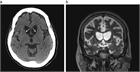

1. 認知症、舞踏運動、精神症状がみられ、頭部CT、MRIにて尾状核頭の萎縮がみられたら本疾患が疑われる。